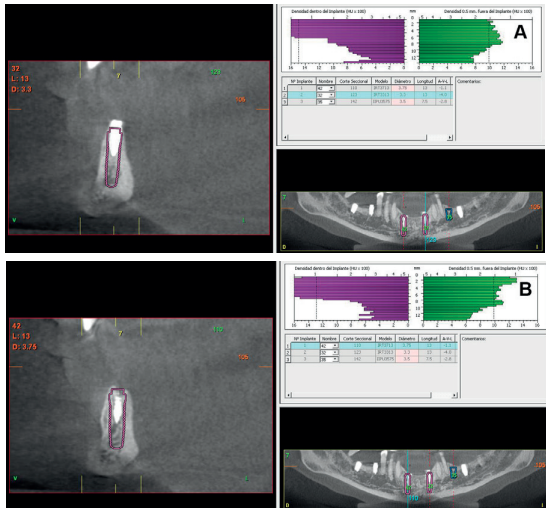

Aft er 4 years, the second and third quadrant molars began to have excessive mobility and serious periodontal problems, so it was decided to remove them and regenerate the alveoli with PRGF-Endoret. Once the area was regenerated (a month and a half later), a conebeam was performed to evaluate the residual bone volume. It can be seen how there was an uneven bone crest with areas of 3.3 mm in height up to a maximum of 7 mm (Figures 9 and 10). On this occasion, due to the protocol change described above, we opted for the direct insertion of extra-short implants, since the surgical protocols to address this type of situation in 2011 varied substantially, with these implants being a first-line tool for the treatment of this type of atrophy (Figure 11). Two extra-short implants were selected (5.5 mm diameter x 6.5 mm length for tooth 26, and 6 mm diameter x 5.5 mm length for tooth 27).

After two months, the dental conebeam showed the perforation had closed completely but the residual bone volume provided 2 mm of bone height only, which was insufficient to insert the implants (Figures 3 and 4).

horizontal resorption of the antero-inferior sector in the incisor

area; (A) area corresponding to tooth 42 (B) area corresponding

to tooth 32 (C) Planning of the expander implant in the CT cut.